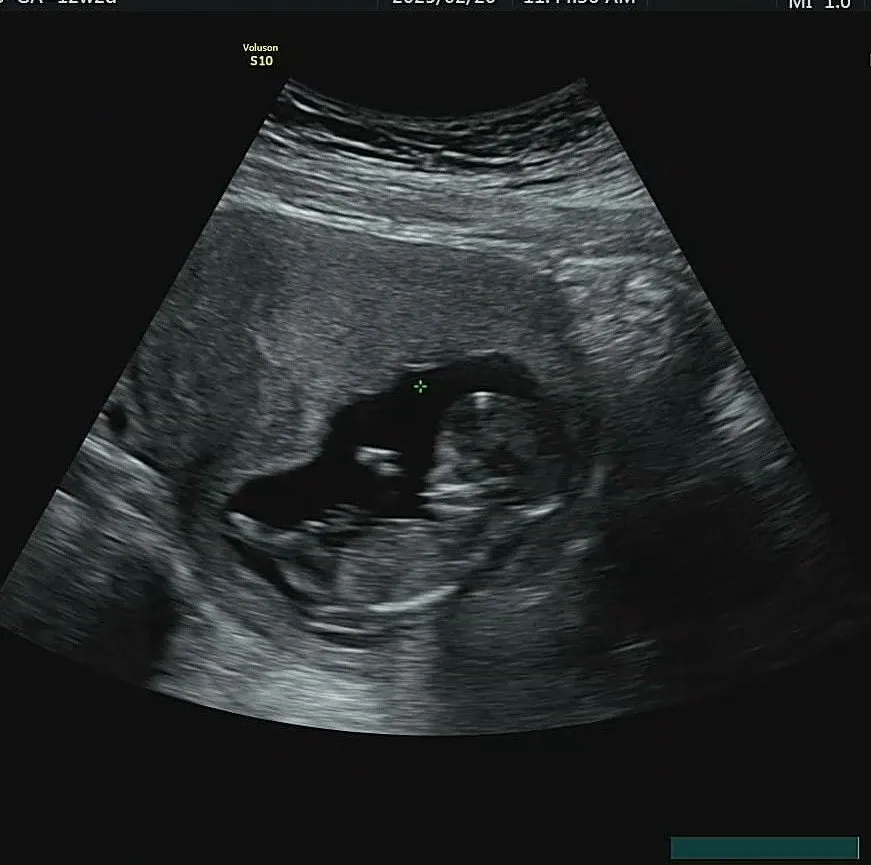

어느덧 임신 12주가 되어 1차 기형아 검사를 했다.

초음파를 볼 때마다 아기의 심장이 뛰는지부터 찾는데, 이번엔 그럴 필요가 없었다.

배를 꾹 누르는 초음파 기계가 불편했던 건지 아기가 폴짝폴짝 뛰고 있었다.

2주 새에 키도 5. 25cm로 폭풍성장해 있었고,

심장소리도 160 bpm으로 정상이었다.

콧대도 잘 형성되어 있는 모습이었고 목투명대도 세 번 연달아 체크했을 때 1.2mm, 1.4mm로 정상이라고 했다.

선생님이 화면을 멈추고 자세히 살펴볼 때마다 선생님의 얼굴을 살피느라 바빴다. 혹시나 안 좋은 소리를 들을까 봐 조마조마했는데 아기도 잘 움직이고 괜찮다고 해주셨다.